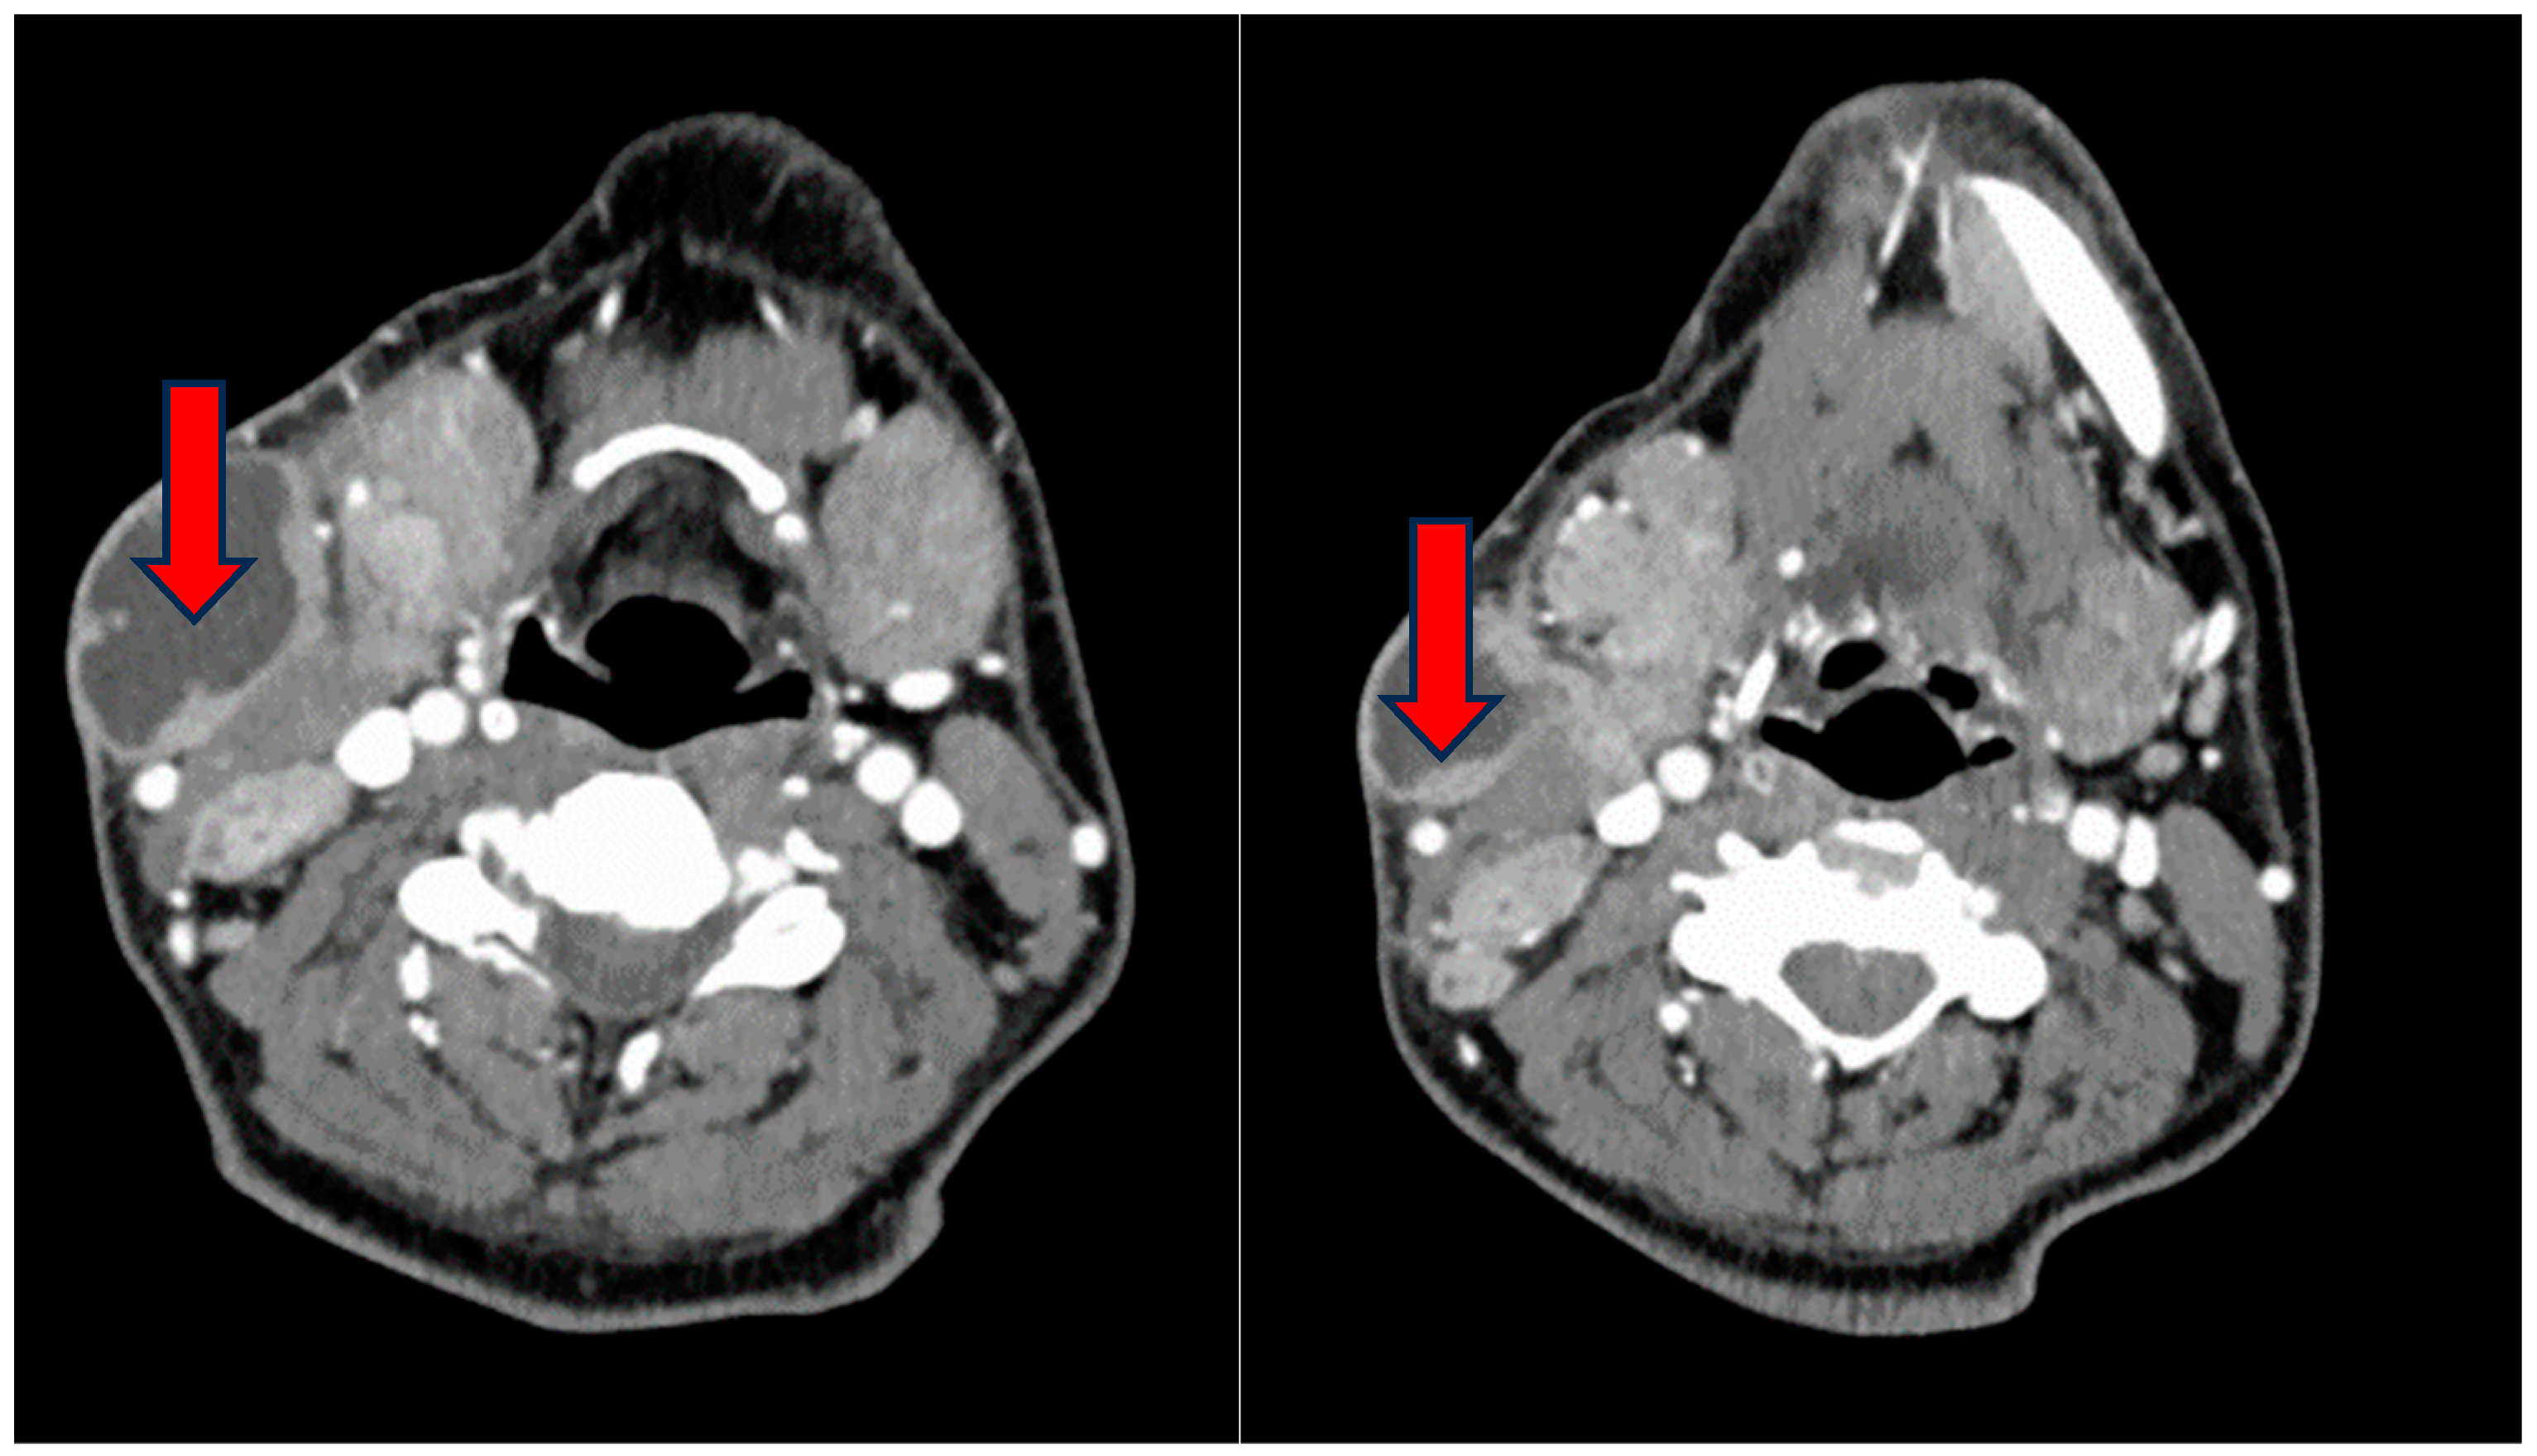

During the physical examination, a notable swelling was observed on the left side of the neck, exhibiting characteristics of softness and tenderness upon palpation, with a diameter of at least 10 cm. Furthermore, the examination revealed hypertrophy and erythema of the right tonsil, notable for the absence of exudate. A neck ultrasound was performed, revealing the presence of two colliquated lymph nodes in the right lateral-cervical region. Subsequent CT imaging confirmed the existence of a conglomerated centrally colliquated mass, extending anteriorly and posteriorly to the sternocleidomastoid muscle, measuring 8 × 4.4 × 10 cm (Figure 1). Additionally, a second lesion was identified in the posterior lateral-cervical homolateral region.

Figure 1.

Neck CT scan confirming a conglomerated centrally colliquated mass (red arrows), extending anteriorly and posteriorly to the sternocleidomastoid muscle of 8 × 4.4 × 10 cm.